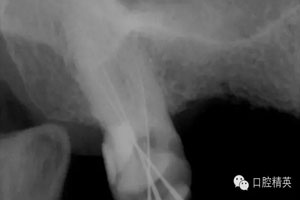

圖1患牙RCT中